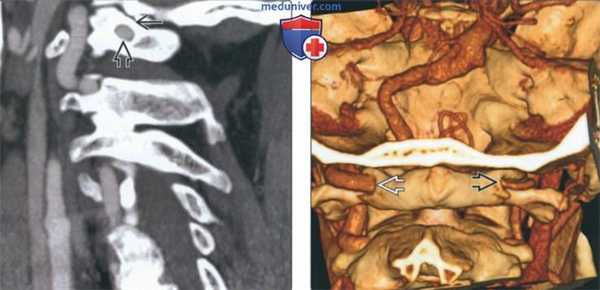

(Слева) На сагиттальной КТА визуализируется замкнутый костный мостик (аномалия Киммерле, полный вариант) над позвоночной артерией, расположенный вдоль верхнего края дуги С1.

(Справа) На трехмерной реформатированной КТА (вид сзади) визуализируются позвоночные артерии: левая (доминирующая) и правая (меньшего размера, недоминирующая). Обе артерии ограничены замкнутым костным мостиком вдоль верхнего края дуги С1.